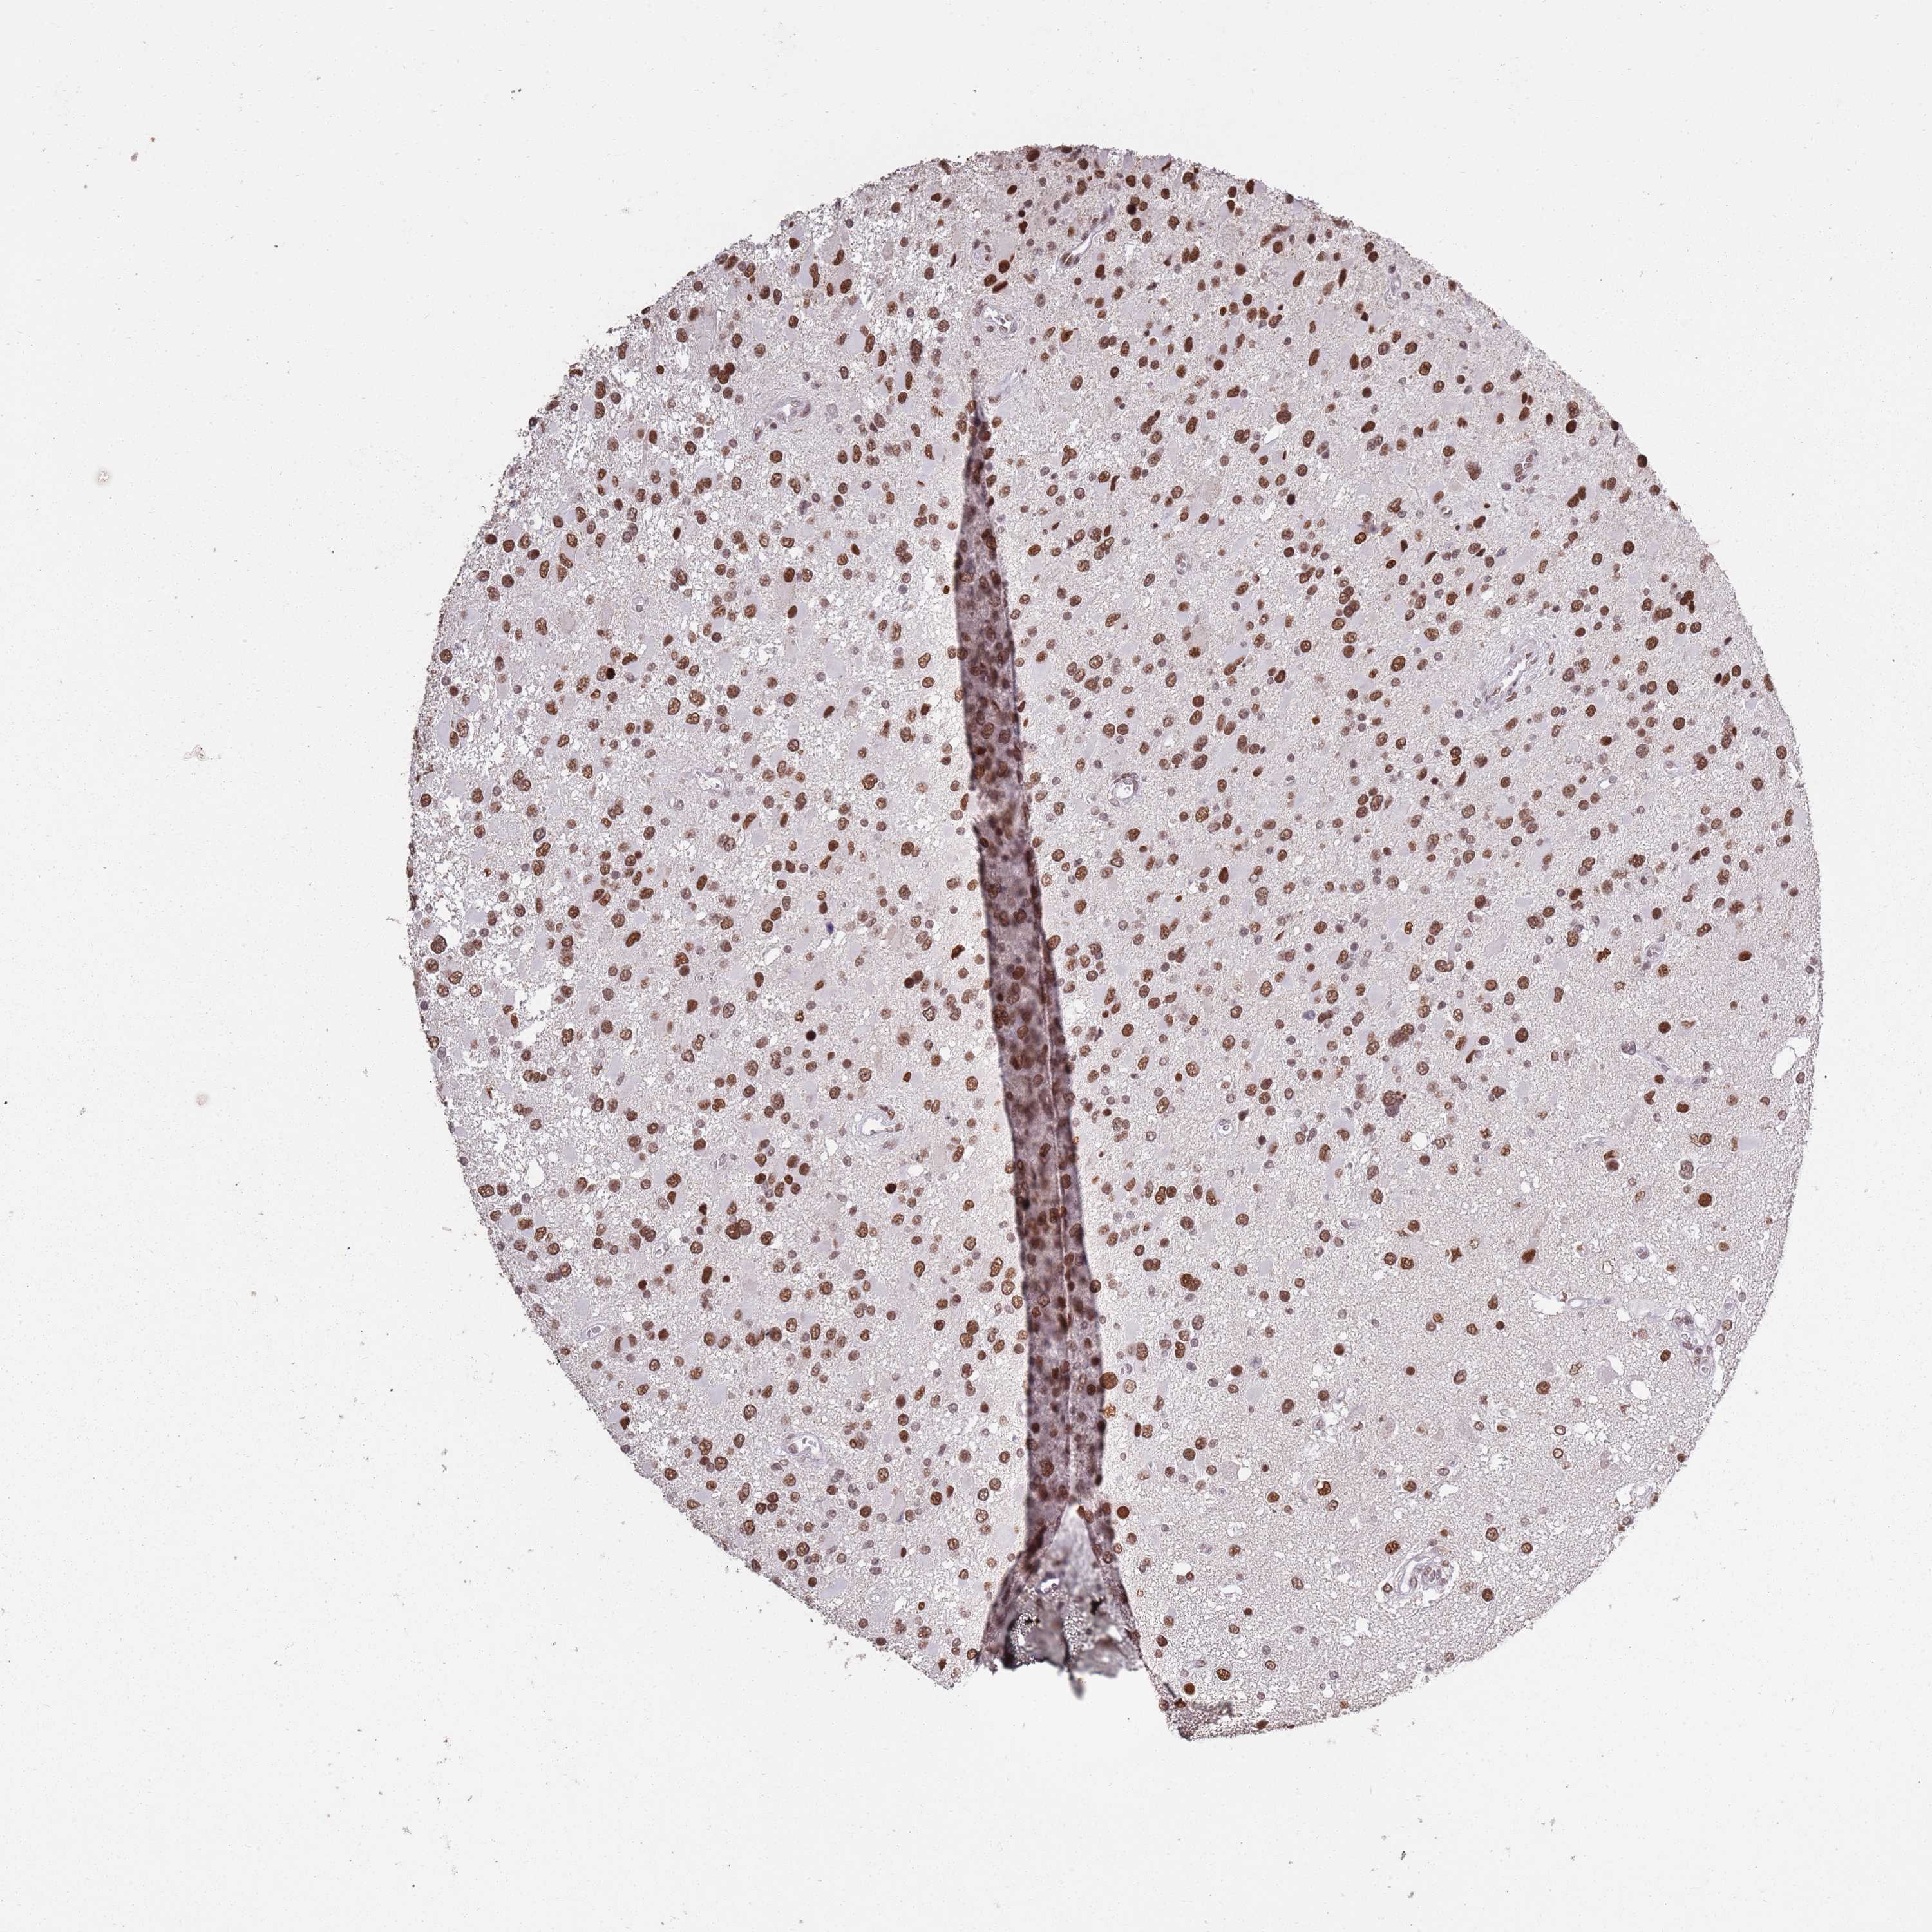

GLIOMA - Protein expressioni

A mouse-over function shows sample information and annotation data. Click on an image to view it in a full screen mode. Samples can be filtered based on level of antibody staining by selecting one or several of the following categories: high, medium, low and not detected. The assay and annotation is described here.

Note that samples used for immunohistochemistry by the Human Protein Atlas do not correspond to samples in the TCGA dataset.

Antibody stainingi

Antibody staining in the annotated cell types in the current human tissue is reported as not detected, low, medium, or high, based on conventional immunohistochemistry profiling in selected tissues. This score is based on the combination of the staining intensity and fraction of stained cells.

Each image is clickable and will lead to virtual microscopy that enables deeper exploration of all samples and also displays staining intensity scores, fraction scores and subcellular localization as well as patient and tissue information for each sample.

Antibody HPA039634

Antibody HPA048127

Staining

High

Medium

Low

Not detected

Intensity

Strong

Moderate

Weak

Negative

Quantity

>75%

75%-25%

<25%

None

Location

Nuclear

Cytoplasmic/membranous

Cytoplasmic/membranous,nuclear

Glioma, malignant, High grade

Glioma, malignant, Low grade